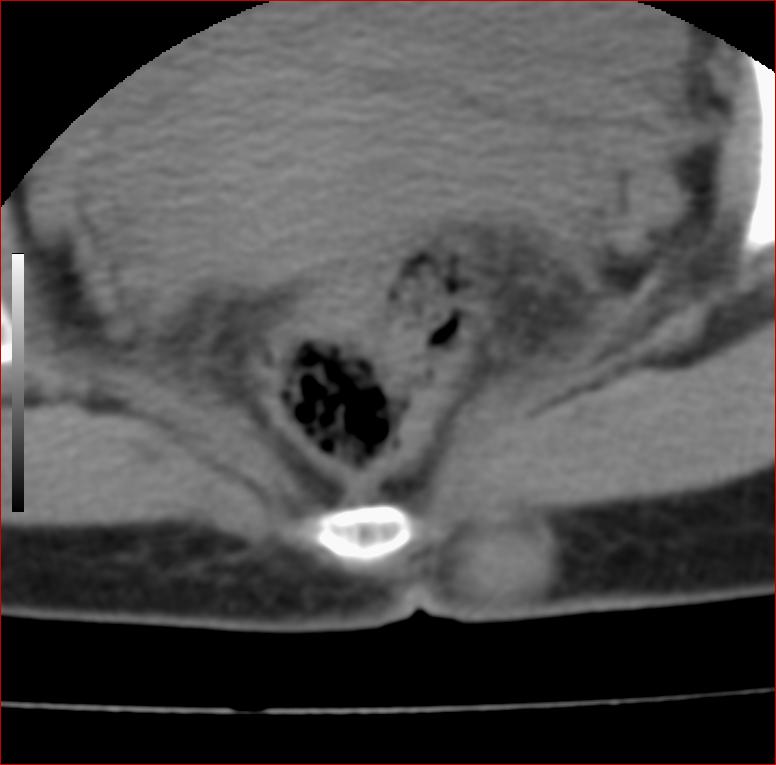

以下是引用13081830109在2007-5-16 18:51:00的发言:[br]良性病变[br]1.皮下皮脂腺囊肿[br]2.纤维瘤[br] 手术切掉就可以了

以下是引用zhangzhongshou在2007-5-16 18:21:00的发言:[br]皮下囊肿可能性大

以下是引用一个人在2007-5-16 20:35:00的发言:[br]1.皮下皮脂腺囊肿[br]2.纤维瘤[br]

以下是引用xulianj在2007-5-16 22:03:00的发言:[br]1皮下皮脂腺囊肿[br]2纤维瘤[br]3还需要除外发育畸形,如脊膜膨出。